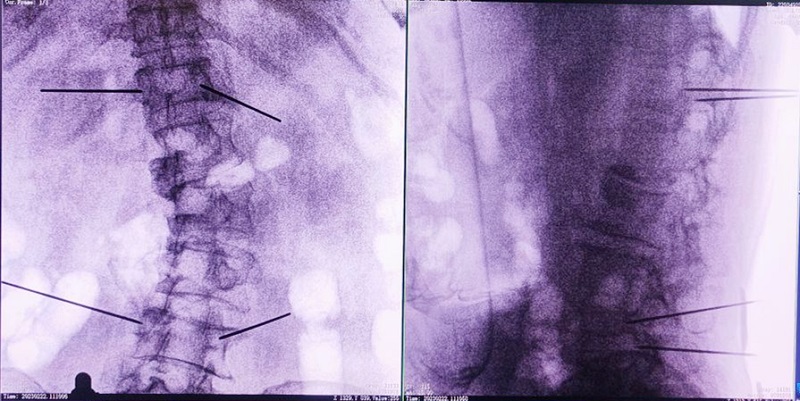

機器人輔助下椎體成形術(shù),是以手術(shù)機器人智能機械臂為基礎(chǔ),仿照經(jīng)皮骨水泥椎體成形術(shù)的施術(shù)步驟,限定穿刺點、穿刺方向、角度和深度,使穿刺針經(jīng)過安全路徑進入目標(biāo)區(qū)域,然后進行骨水泥注入,輔助手術(shù)設(shè)計、精準(zhǔn)指導(dǎo)手術(shù)實施。以普愛醫(yī)療的骨科手術(shù)機器人PL300B為例,其輔助進行的一例胸腰椎壓縮性骨折經(jīng)皮椎體成形術(shù)的過程如下:

(1)首先使用普愛醫(yī)療三維C形臂采集胸腰椎病灶三維圖像,對傷椎進行三維重建;

(2)醫(yī)生制定個性化的手術(shù)方案,在機器人導(dǎo)航界面上進行路徑規(guī)劃;

(3)根據(jù)設(shè)定好的的位置和入針方向,植入引導(dǎo)針;

(4)所有引導(dǎo)針植入完畢后,沿引導(dǎo)針方向進行椎弓根及椎體置管,建立通道;

(5)沿通道注入骨水泥,恢復(fù)椎體高度,并觀察其擴散情況,達到滿意效果后,停止注入骨水泥。